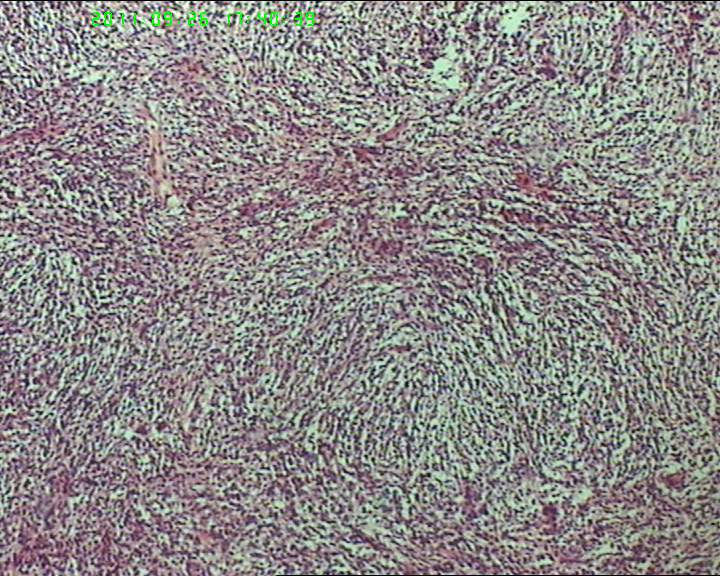

包块与大网膜粘连,根部附着于肠系膜,脾曲处有较多积血块 但无活动性出血,肠系膜上有较多粟粒样结节,白色质韧。与子宫 输卵管 卵巢没有关系.

灰白不整形肿物一个,大小18*15*9cm,表面结节状,包膜完整,切面灰白,中央可见坏死区,质软,范围5*4cm。其余切面多彩 部分半透明状 质中。

鉴别诊断排排队:1、GIST,2、MPNST,3、去分化脂肪肉瘤,4、恶性间皮瘤,5、恶性SFT,6、平肉

主要考虑前二者。CD34,CD117,S-100,BCL-2,SMA, D2-40,CR, VIM. 结果如何?请楼主揭谜底吧。